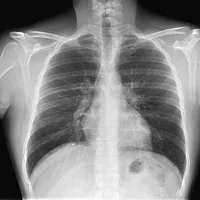

Preguntas sobre Radiografía de Tórax

¿Cuál de las siguientes estructuras se considera normalmente transparente a los rayos X (radiolúcida) en una radiografía de tórax PA?

En una radiografía de tórax PA, ¿qué lado del diafragma suele estar ligeramente más elevado?

¿Cuál es el propósito principal de una radiografía de tórax en proyección PA (Posteroanterior)?

¿Cuál de las siguientes es una característica normal de los hilios pulmonares en una radiografía de tórax PA?

¿Qué representa la silueta cardíaca en una radiografía de tórax PA?

¿Cómo deben aparecer los campos pulmonares en una radiografía de tórax normal?

En una radiografía de tórax PA, ¿cuántas costillas posteriores completas (desde la unión costo-vertebral) se deben observar típicamente por encima del diafragma para una inspiración adecuada?